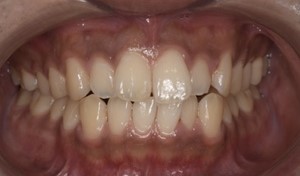

Before

After

基本情報

| 主訴 | 見た目をきれいにしたい |

| 治療期間 | 6ヶ月 |

| 治療費 | ジルコニアボンド(セラミックの被せもの)¥165,000×7(税込み) オフィスホワイトニング4回 ¥4,400×4(税込み) ホームホワイトニング¥11,000 |

| リスク・副作用 | かみ合わせがとても強い方の場合、稀に割れてしまうことがあります。 |

| 先生からの提案 | 上の前歯6本と右下の2番目の歯はセラミックの被せもので治療。 残りの下の前歯5本はプラスチックの材料で虫歯を治療し、 ホワイトニングをおこないました。白くなったご自身の歯の色に合わせてセラミックの 被せものを作成しています。 模型上で完成後をシュミレーションし、上の歯茎の位置をきれいに見えるように 揃えています。(外科処置はしていません) |